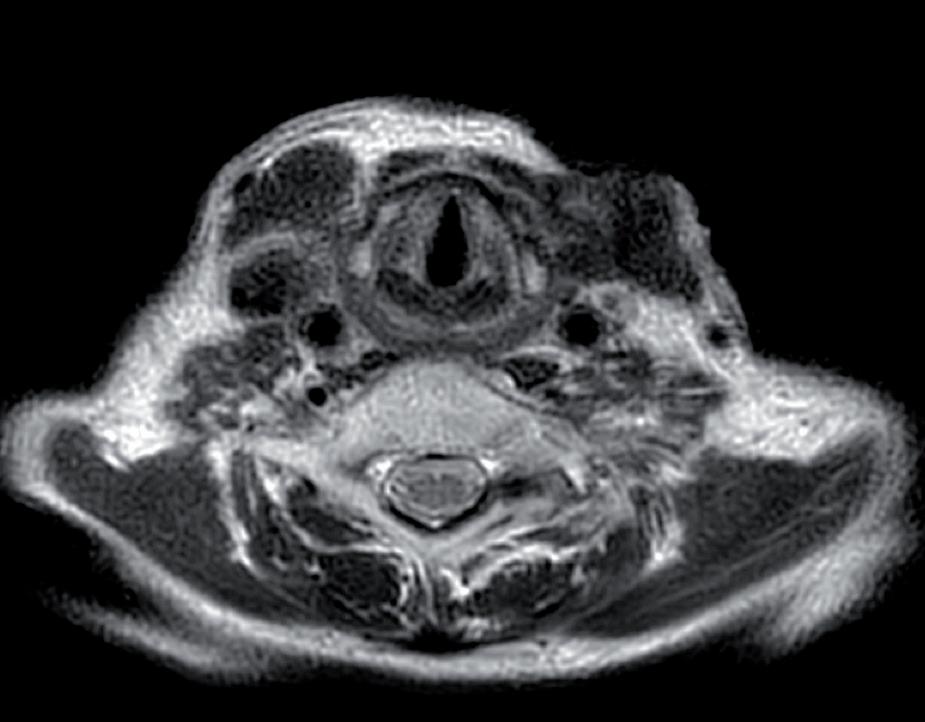

Agosto 2021 PET total body con FDG: “ipercaptazione orofaringea e linfonodale laterocervicale bilaterale” (figure 1 e 2).

Figura 1. PET total body con FDG mostra ipercaptazione orofaringea e linfonodale laterocervicale bilaterale.